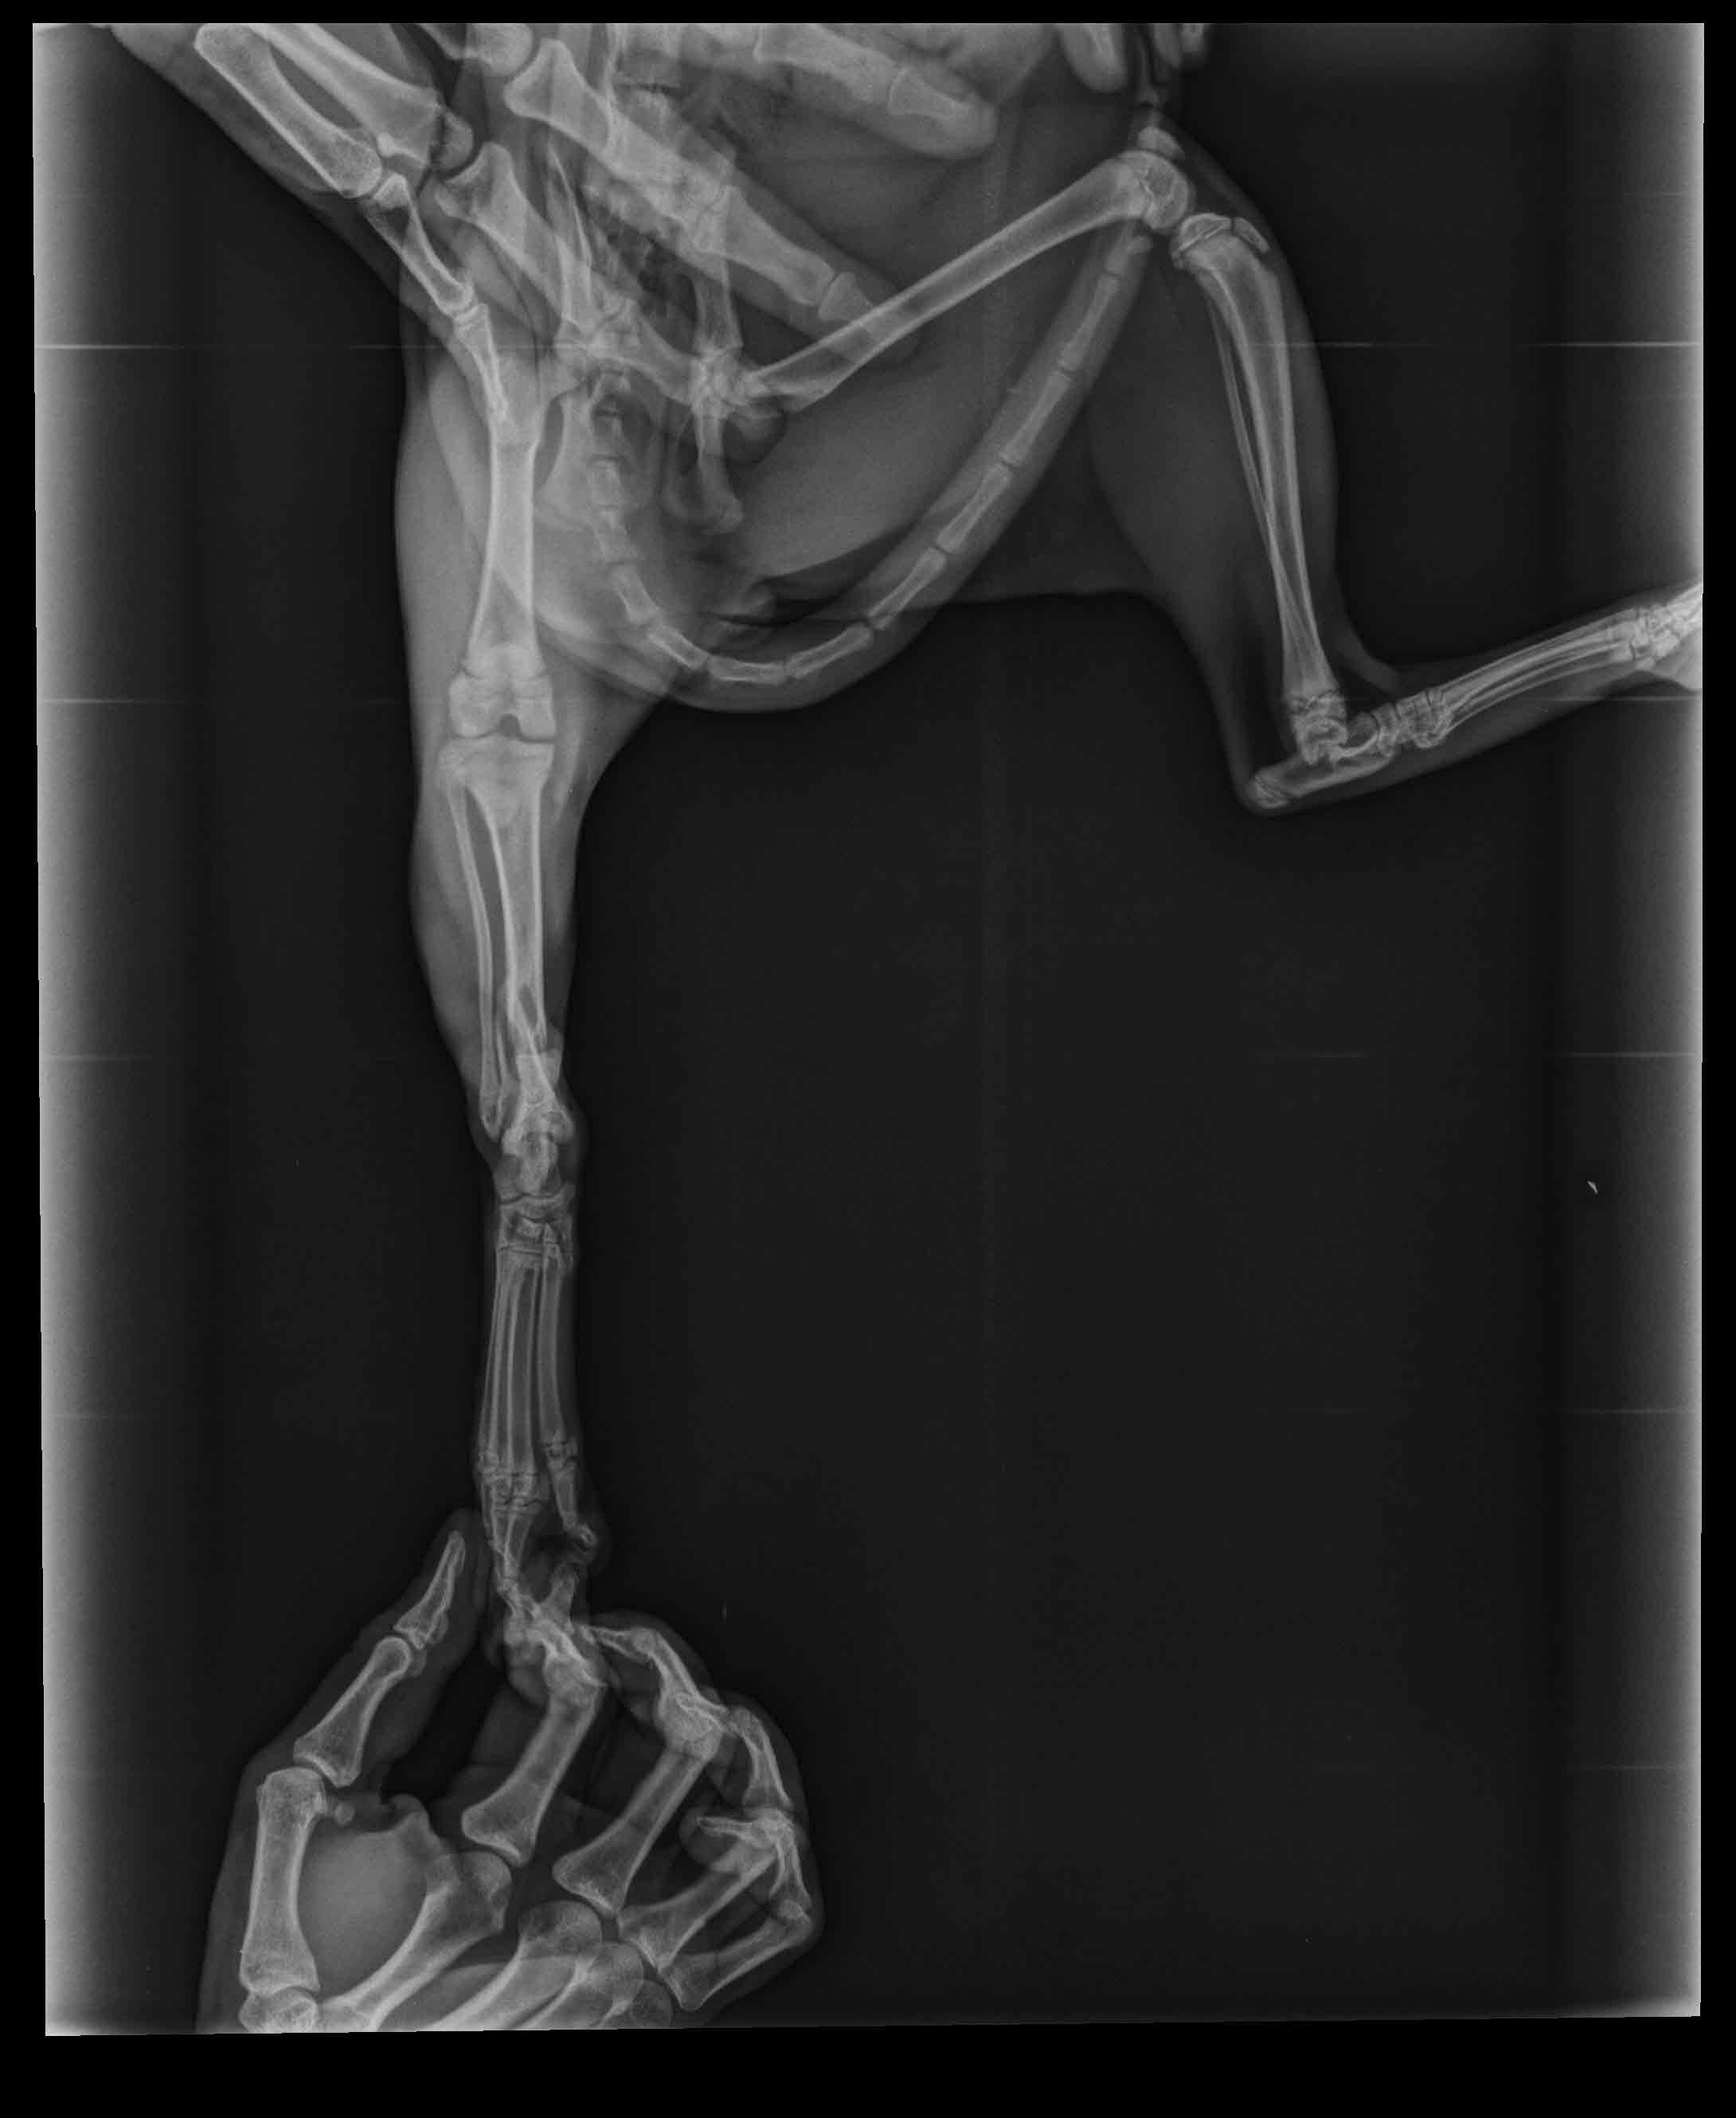

Hello, I have a five months male cat. While he was playing on the table, accidently he fallen down and screamed. After he stand up he start to not stepping on the foot. After veterinary control, they said his foot bone was broken. But i am not sure that it is true. In our country the veterinaries can lied about the situation for earning much money. I atteached the x-ray. Could you check is there a fracture?

I am pretty sure I can see a fracture of the tibia. If you look closely at the third picture and compare the two legs, the long bone right above the foot does not look the same as the other leg. These fractures can usually be healed with splinting or surgery, cage confinement, and pain management.

I am very sorry to hear about your kitty. Unfortunately it does appear he has a broken bone, though in the photo the bone I see broken is actually his leg bone- not the foot. If you look at the bones just above the foot/ankle, the larger of the two long bones has a fracture (this is the tibia). We would need to see an additional view of the bone to know how displaced the fracture is and the best course of action to repair the break.